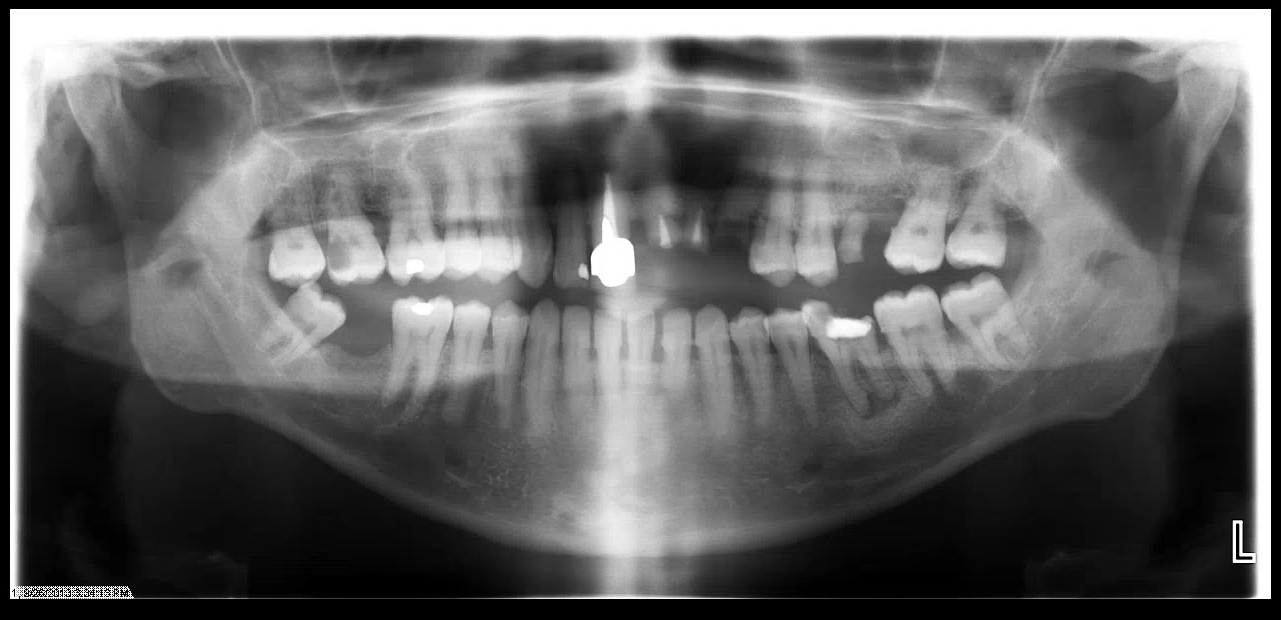

- Periodontal: Evaluate bone loss and need for therapy beyond prophylaxis

- Orthodontics/Prosthodontics: Pt. has Class III Occlusion and missing #2, 8, 9, 10, 11, 14, 19 and 31

- Implants for anterior maxillary teeth with bone and tissue graft (#8, 9, 10 and 11)

- Single unit implants for #2 (sinus lift needed), #19 and #31